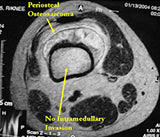

MRI:

- Mass on surface of bone

- Intermediate signal on T1 weighted images and high signal on T2 consistent with cartilage

- Usually no intramedullary invasion but may see slight erosion or saucerization of cortex

- Periosteal reaction evident on MRI as very low signal on T1 and T2 weighted images